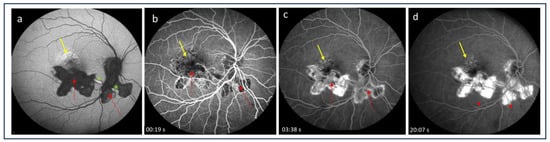

- Hoang, Q.V.; Cunningham, E.T., Jr.; Sorenson, J.A.; Freund, K.B. The “pitchfork sign” a distinctive optical coherence tomography finding in inflammatory choroidal neovascularization. Retina 2013, 33, 1049–1055. [Google Scholar] [CrossRef] [PubMed]

- Christakopoulos, C.; Munch, I. The ‘pitchfork sign’ on optical coherence tomography in a case of acute syphilitic posterior placoid chorioretinitis. Acta Ophthalmol. 2019, 97, e942–e943. [Google Scholar] [CrossRef]

- Rajabian, F.; Arrigo, A.; Grazioli, A.; Sperti, A.; Bandello, F.; Battaglia Parodi, M. Focal choroidal excavation and pitchfork sign in choroidal neovascularization associated with choroidal osteoma. Eur. J. Ophthalmol. 2021, 31, NP67–NP70. [Google Scholar] [CrossRef]

- Berensztejn, P.; Brasil, O.F. Re: The ’pitchfork sign’ a distinctive optical coherence tomography finding in inflammatory choroidal neovascularization. Retina 2015, 35, e23–e24. [Google Scholar]

- Falavarjani, K.G.; Au, A.; Anvari, P.; Molaei, S.; Ghasemizadeh, S.; Verma, A.; Tsui, I.; Sadda, S.; Sarraf, D. En face OCT of Type 2 neovascularization: A reappraisal of the pitchfork sign. Ophthalmic Surg. Lasers Imaging Retin. 2019, 50, 719–725. [Google Scholar] [CrossRef]